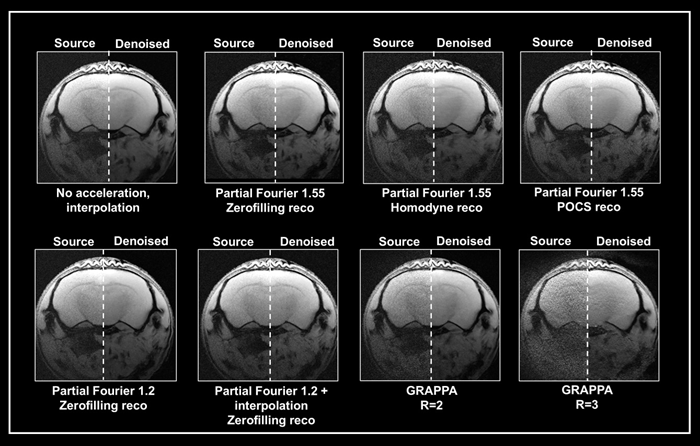

Ex vivo brain data were collected using either partial Fourier or the multi-coil generalized auto-calibrating partial parallel acquisition (GRAPPA) method (Fig 5). The data obtained without acceleration served as a reference. Acceleration resulted in up to a threefold reduction in acquisition times compared to the protocol without averaging.

Denoising of accelerated brain data

Figure 5. Denoising of accelerated brain data. Ex vivo T1-weighted FLASH data of a fixed mouse head were acquired at 9.4 Tesla. Data were either acquired with no acceleration, with partial Fourier (in Read), partial Fourier and interpolation (1.35 in Read and Phase), or with multi-coil parallel imaging technique GRAPPA. For GRAPPA, an acceleration factor (R) of 2 and 3 was chosen, respectively. Partial Fourier images were reconstructed either with zerofilling, homodyne, or POCS, as indicated. All images are shown with no denoising (Source) and after denoising (Denoised) with a Strong network, applying a pre-denoising level of 50 % and denoising level of 70 %. Image Credit: Bruker BioSpin Group

A denoising level of 70% resulted in greater residual noise in data acquired with a partial Fourier 1.55 than in data acquired without acceleration. The effect was largest in homodyne-reconstructed data and weaker in zero-filled data.

Denoising of these accelerated datasets resulted in image blurring, which was largest in homodyne reconstructed images and lowest in zerofilling reconstructions.

When images were acquired using partial Fourier 1.2, they had less residual noise and appeared normal when denoised with 70%. Denoising, on the other hand, was ineffective when combining a partial Fourier with interpolation (1.35 in Read and Phase) and the source and denoised images had comparable appearances.

Grappa acceleration produced noisier images compared to partial Fourier capture. Reconstructing the collected data using the denoising method successfully reduced noise from the GRAPPA image acquired with an acceleration factor of 2.

However, in the image captured with an acceleration factor of 3, the noise is not totally erased. Moreover, reconstruction artifacts and loss of tissue contrast unrelated to the denoising reconstruction are visible.

This suggests that the method may be unable to deal with data with noise characteristics that differ from those used to train the networks. However, the outcome is determined by the parameters used for acquisition and reconstruction.